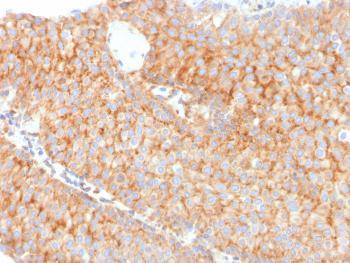

Fig. 1: Formalin-fixed, paraffin-embedded human Urothelial Carcinoma stained with PAI-RBP1 Mouse Monoclonal Antibody (SERBP1/3491).

Western Blot (1-2ug/ml); ,Immunohistochemistry (Formalin-fixed) (1-2ug/ml for 30 minutes at RT),(Staining of formalin-fixed tissues requires heating tissue sections in 10mM Tris with 1mM EDTA, pH 9.0, for 45 min at 95 °C followed by cooling at RT for 20 minutes),